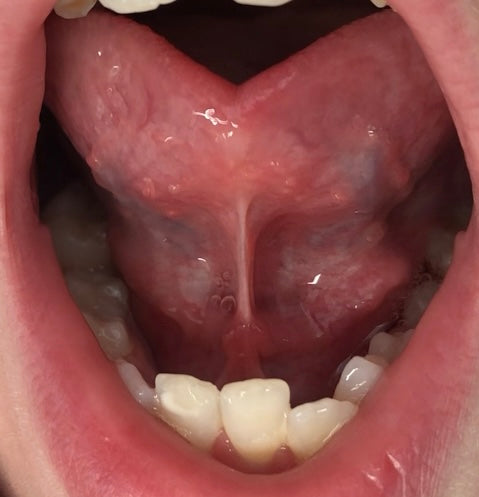

Ein verkürztes Zungenband betrifft nicht nur Babys oder Kinder.

- Bewegungsumfang der Zunge

- Ruheposition

- Schluckmuster